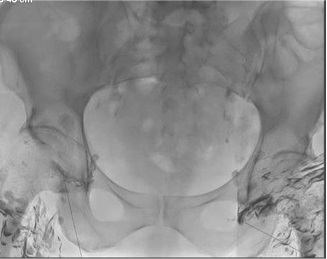

4. 透视下手推缓慢注射(Slow hand injection (0.5 ml Lipiodol / min) under fluoroscopic guidance)

手注碘油,每隔5分钟,注射1ml碘油,每个淋巴结注射总量在3-6mL,注射时,不时透视确认针位。

NL- Lipiodol injection